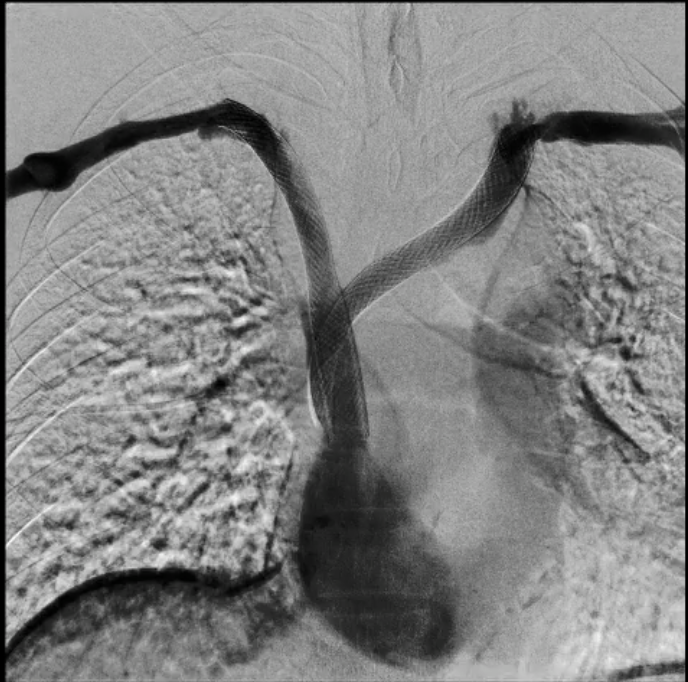

Bilateral venography demonstrated complete occlusion of both brachiocephalic veins with extensive collateral formation.

Real-time echo-guided puncture of both basilic veins was performed, and 6 Fr sheaths were inserted bilaterally. Bilateral venography demonstrated complete occlusion of both innominate veins with extensive collateral formation. A V-18 wire was advanced through the left brachiocephalic vein lesion, followed by a Sterling 5.0 ¡¿ 80 mm balloon inflated to 12 atm from the SVC to the left brachiocephalic vein for angioplasty. The wire was then exchanged for a Connect Flex 0.018¡È ¡¿ 300 cm wire to cross the right brachiocephalic vein lesion toward the internal thoracic connection (ITC). A Sterling 5.0 ¡¿ 80 mm balloon was inflated to 10 atm from the SVC to the right brachiocephalic and right axillary veins for angioplasty; however, the right axillary vein lesion failed to dilate adequately. A Mustang 10 ¡¿ 80 mm balloon was subsequently used and inflated to 20 atm, yet residual stenosis persisted. The wire was exchanged for a Roadrunner wire, and a Conquest 40 balloon was advanced and inflated to 30 atm for high-pressure angioplasty of the right innominate, axillary, and cephalic veins. Subsequently, Wallstent 16 ¡¿ 90 mm was deployed from the SVC to the left brachiocephalic vein, and Wallstent 14 ¡¿ 90 mm was deployed from the SVC to the right brachiocephalic vein. Final post-dilatation was performed using a Mustang 12 ¡¿ 80 mm balloon inflated to 10 atm for both brachiocephalic vein stents.

Successful endovascular revascularization was achieved in a patient with superior vena cava syndrome secondary to chronic bilateral brachiocephalic vein occlusion. High-pressure balloon angioplasty followed by bilateral stent deployment restored venous patency and relieved symptoms. This case highlights the feasibility and effectiveness of endovascular therapy in dialysis-related chronic central venous obstruction.